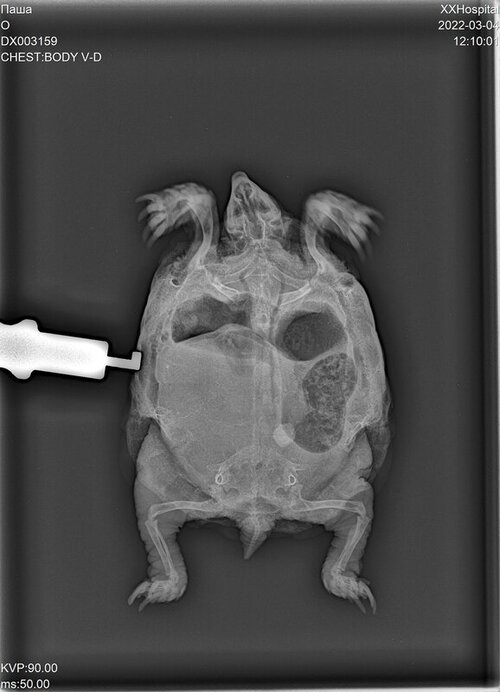

черепаха среднеазиатская, 14см, пол М

Жалобы: начал окрывать рот и запрокидовать голову, раздулся сильно.

состояние не улучшается, но рот открывать и запрокидывать голову перестал, дышит ровно, отечность сохраняется преимущественно слева.

при передвижении задние лапы не использует, но отдельно ими шевелить может. Ест листовой салат. Опоржение происходит жидкостью после введения препаратов. Лапы достаточно сильные - слабости у питомца не наблюдается

Лечение на фото, рентген, фото сегодня. Все фото прикреплю в комментариях

DX003159_1.JPG